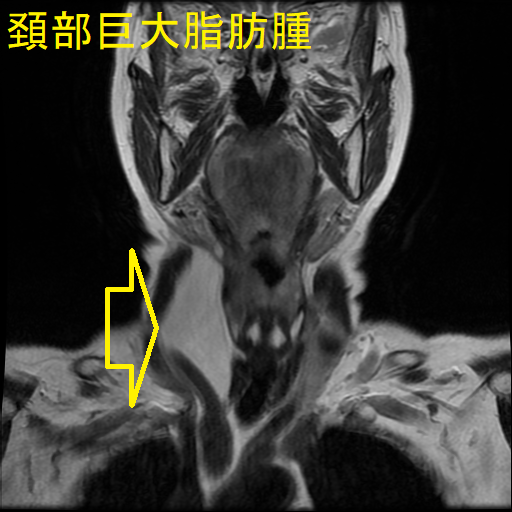

巨大頚部脂肪腫